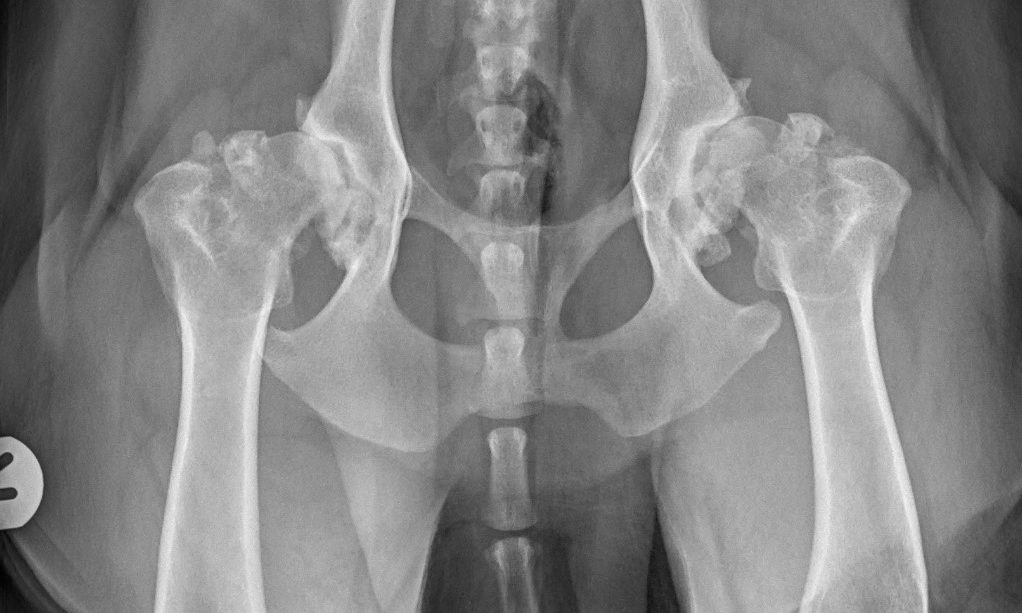

โRottweilers top the lame listโ, says RVC

Rottweilers are the most predisposed dog breed to suffer from osteoarthritis according to new research from the Royal Veterinary College (RVC). Osteoarthritis is the most common joint disease diagnosed in dogs, and this study is the largest ever conducted into the condition in dogs under veterinary care โ covering 455,557…